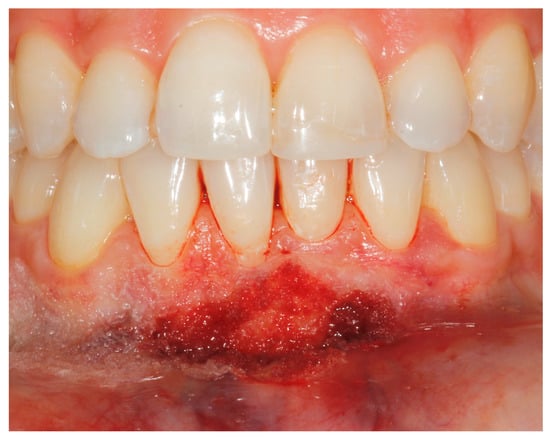

2. Case Study

- (a)

- deep partial thickness incision (blade parallel to the periosteum) made at the level of the external insertion of the frenulum;

- (b)

- elimination of superficial mucous tissue and muscle of the frenulum;

- (c)

- a series of detached points with periosteal anchorage for the apical positioning of the lining mucosa of the lip and the second intention healing of the exposed periosteum.